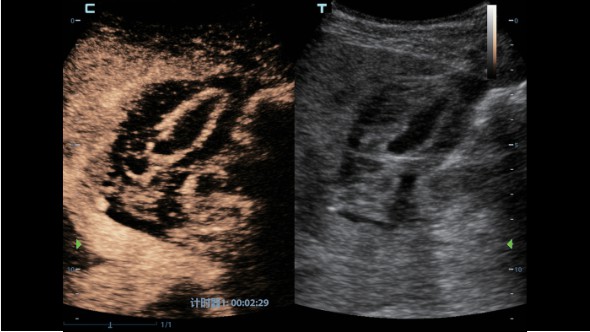

Клинические изображения